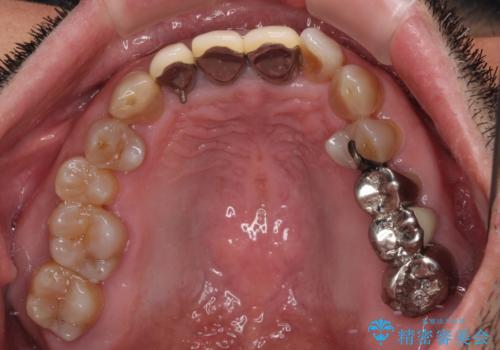

- 幼少期の薬剤の影響で歯が変色していていることを気にして来院された患者様です。

仕事も落ち着き、長年気にしていた前歯の色をきれいにしたいとのことでした。

上下ともに前歯のセラミッククラウンによる補綴治療を希望されていましたが、下顎前歯は叢生が強いため、補綴治療前に部分矯正を行って歯列を整えた上で、補綴治療を行うこととしました。

臼歯部には歯周ポケットのある箇所が散見されましたが、まずは前歯を治療したいとのことで、治療を進めました。